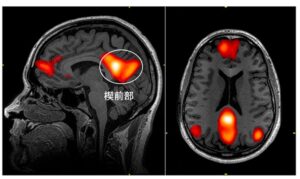

下の図は、スキーマの獲得に関わる脳領域について図示したものですが、

引用:Gilboa A, Marlatte H. Neurobiology of Schemas and Schema-Mediated Memory. Trends Cogn Sci. 2017;21(8):618-631. doi:10.1016/j.tics.2017.04.013

脳の中でも、意味処理に関わる側頭葉の前部領域、様々な感覚情報の統合に関わる頭頂葉の角回、意思決定に関わる腹側内側前頭前野がスキーマの獲得に関わっていることが示されています。

側頭葉というのは意味処理に関わる領域なのですが、

側頭葉でも前に方に行けば行くほど、抽象度の高い意味情報(例えば、愛や正義、悪などの意味)の処理に関わるとされています。

スキーマの理解に際しては、この深い意味を処理する側頭葉の前の方の領域が活動することが示されています。

また頭頂葉は一般に様々な感覚情報がまとめられる領域なのですが、その頭頂葉の中でも角回というのは情報統合のまとめ役的なポジションにおり

やはりスキーマという抽象度の高い情報を認識するときに活動することが示されています。

また前頭前野も様々な情報が取りまとめられる領域ではあるのですが、その中でも右脳と左脳がくっつく脳の内側面にある腹側内側前頭前野は、情動に関わる情報と理知的な情報を取りまとめるような場所に位置しています。

このように脳の様々な領域の中枢に当たる場所が、スキーマの理解に関わっていることが示されています。